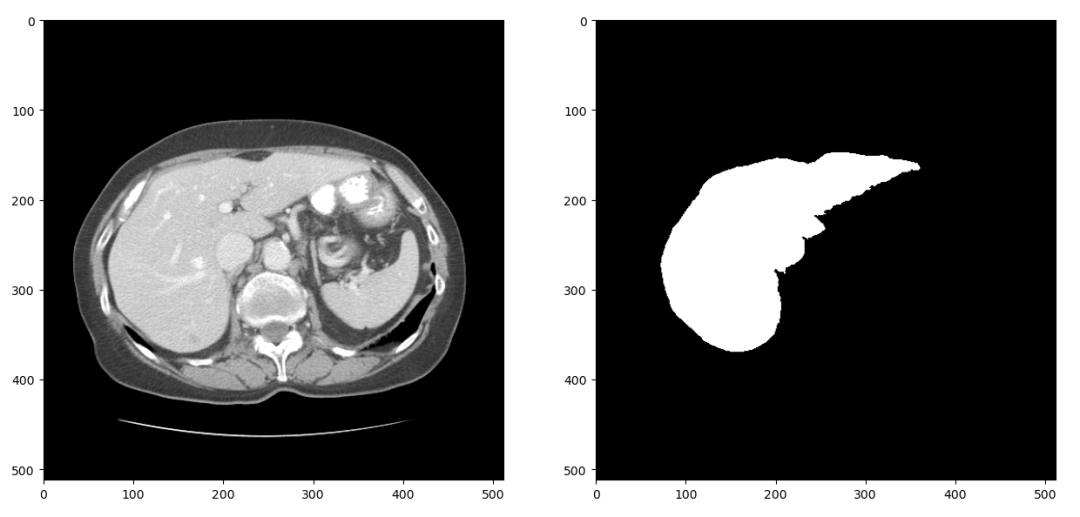

上述的Res-Unet结构是一个2D的分割网络,因此我们首先将LiTS数据集中3D的CT扫描分成2D的切片。CT在拍摄和重建的过程中会引入一些噪声,因此我们只保留-1024到1024范围内的数据。经过这两步处理,可以得到大概1万张CT扫描切片及对应的分割标签,随机选择一组进行可视化结果如下

图4 2D切片